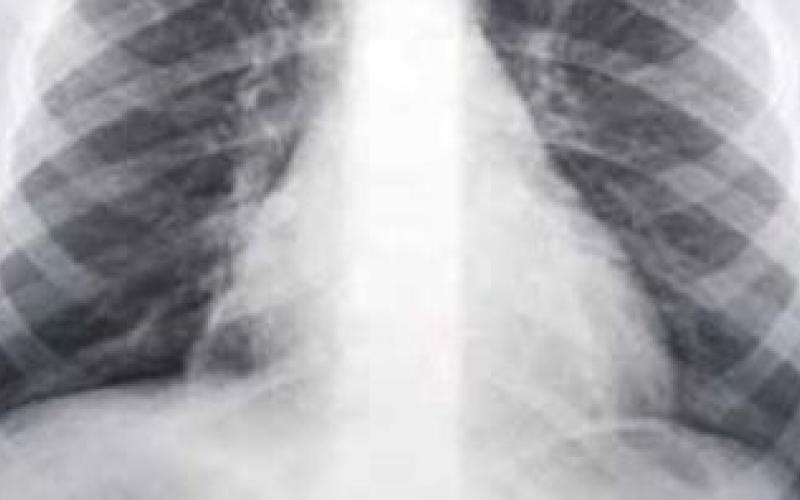

100 ألف إصابة بالالتهابات الرئوية سنويا

قدر مختصون عدد حالات الإصابة بالالتهاب الرئوي بمايتراوح مابين 70-100 الف إصابة سنويا في المملكة.

وحذر من تزايد حالات الإصابة بالالتهابات الرئوية وخاصة في مثل هذا الوقت من السنة، خاصة وانها تودي بحياة 10 بالمئة من المصابين.

واشار إلى أن نسبة الالتهابات الرئوية تصل الى ما يقارب 6 اصابات لكل الف نسمة، وفي كبار السن تصل الى 30 إصابة لكل الف نسمة.

وبين الحسيني انه رغم ان معظم حالات الاصابة يمكن علاجها في العيادة دون الدخول للمستشفى، إلا أن 20 بالمئة من تلك الحالات تستلزم دخول المستشفى، وأحيانا إلى قسم العناية الحثيثة.

ولفت إلى أن نسبة الوفيات جراء الالتهابات الرئوية البكتيرية الشرسة تصل إلى 10 بالمائة من مجموع الاصابات السنوية، وهو ما يزيد من المسؤولية الواقعة على كاهل المجتمع الطبي في تشخيص المرض مبكرا واعطاء العلاجات الملائمة التي تضمن تحسن المريض والقضاء على البكتيريا المسببة.